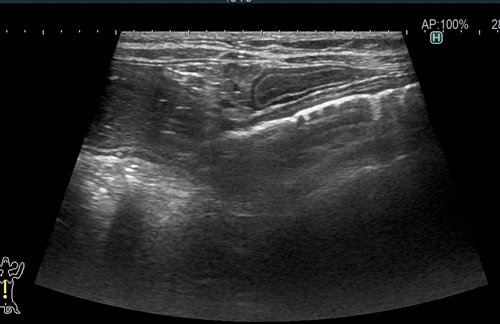

猫の小腸内異物(ジョイントマット)1 症例報告(高橋雅弘) 高橋ペットクリニック外科ケースより 猫の急性嘔吐と食欲不振 超音波検査において 小腸内に表面高エコーで音響陰影を伴っているため異物を疑います。 通過障害を疑う腸管の拡張が見られました。 以上の所見より小腸内異物と診断し、静脈内点滴を実施して緊急手術を行いました。 つづく!! « 前の記事へ カテゴリ一覧ページに戻る 次の記事へ »